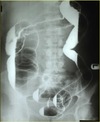

Extracapsular NOF

Extracapsular (intertrochanteric) fracture